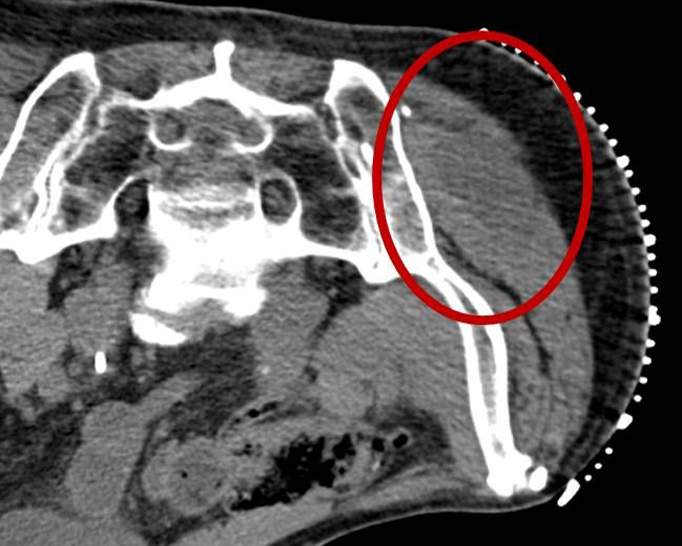

Eine Vielzahl von Krankheitsdiagnosen basiert auf der mikroskopischen bzw. histologischen Untersuchung körpereigener Gewebe, die auf möglichst schonende Weise entnommen und anschließend im Labor bzw. unter dem Mikroskop untersucht werden. Bei der perkutanen Biopsie punktiert der Arzt mit einer dünnen Nadel durch die Haut hindurch ('perkutan') das Zielorgan und entnimmt so eine kleine Menge Flüssigkeit oder ein kleines Gewebestück. Der Eingriff kann im Regelfall in örtlicher Betäubung durchgeführt werden. Um das Zielgewebe möglichst sicher zu treffen, führen wir die meisten Biopsien unter CT-Steuerung, alternativ unter sonographischer Steuerung, durch. Ist die Zielläsion nicht sicher im CT oder im Ultraschall zu erkennen, führen wir die Biopsie mit speziellen Biopsie-Systemen im Einzelfall auch unter MRT-Kontrolle durch.